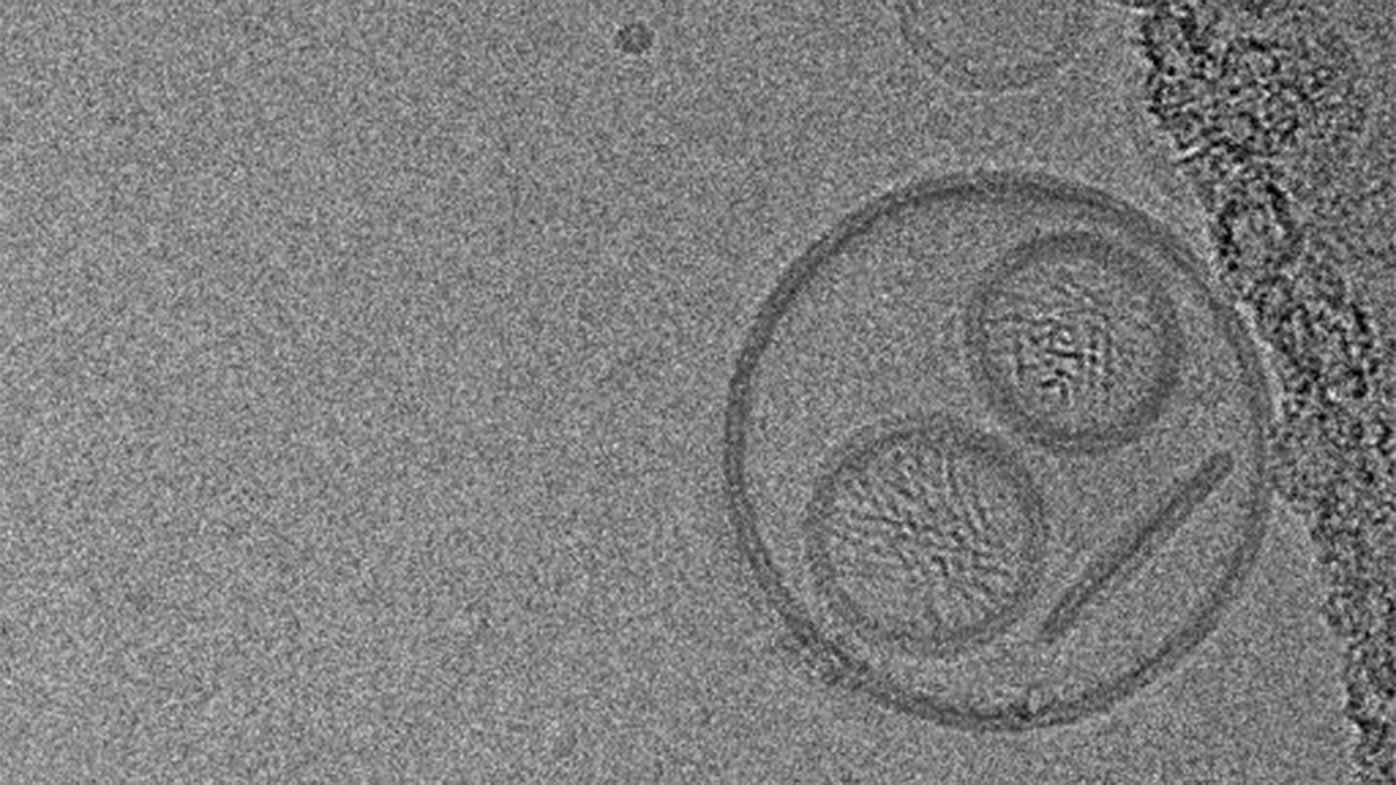

Every day, Bristol Myers Squibb colleagues and scientists come across images that highlight the wonders of science and the cutting-edge work of the company’s research teams. The image here, an unusual capture of a liposome, was submitted by Nanotechnology Scientist Jeffrey O’Brien in Drug Product Development from the company’s R&D facility in San Diego, CA.

A liposome is a nano-sized particle that functions as a membrane, similar to how a cell membrane surrounds a living cell. Using nanotechnology, liposomes can be turned into tiny vehicles for delivering drugs to targets in the body where other medicines can’t go. The liposome in this image was designed to access the lymphatic system.

In the image, the round shape that resembles a head is a liposome. The image also captures something that didn’t go as planned: the liposome expanded and engulfed smaller liposomes, which resemble the eyes and mouth.

“It was pretty funny,” O’Brien said of the image, and noting that the process has since been improved to control liposome growth. “I started putting this image in slide decks as a bit of comic relief. It’s clearly showing something we didn’t want to see, so the joke was that we share the same sentiment as the liposome, and we can do better.”